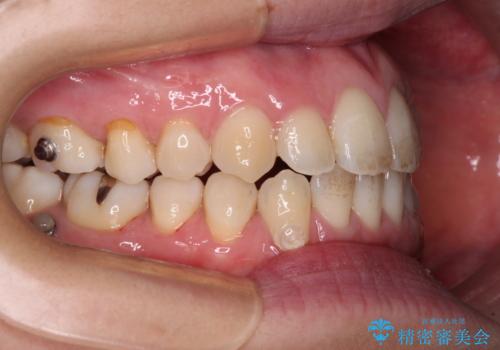

- 受け口傾向でクロスバイトの前歯を治したいとのことで来院された患者様です。

下顎骨が若干左側に変位していたため、右側にアンカースクリューを使用し、積極的に移動させながらインビザラインにて矯正治療を行うこととしました。